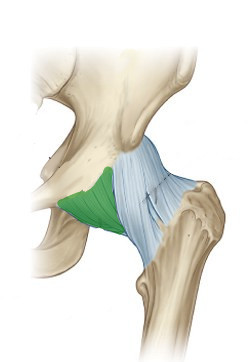

What is this structure?

Ischiofemoral ligament of hip

What is this structure?

Ileofemoral ligament of hip

What is this structure?

Pubofemoral ligament of hip